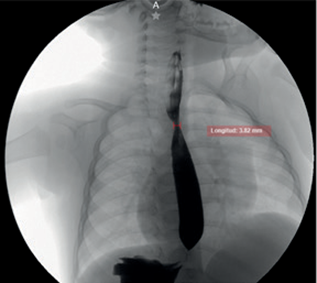

Al examen físico destacó hipotonía generalizada con posición en “libro abierto”, ausencia de sostén cefálico, reflejo plantar de Babinski positivo, clonus inducido, reflejo de Galant y paracaídas positivos, presión palmar y plantar 2/4, y reflejos osteotendinosos 3/4. Dentro de los estudios complementarios se evidenció una TSH en 8.1 mIU/L, por lo que se inició tratamiento con levotiroxina 25 mcg, logrando descenso a 0.03 mIU/L, lo que motivó su suspensión. Además, se detectó serología positiva para Epstein-Barr IgG y se identificó una estenosis parcial del esófago medio (véase Figura 1).

Figura 1. Estudio esofagograma en proyección anteroposterior que muestra una estenosis parcial del esófago medio, evidenciada por una zona de estrechamiento luminal segmentario con paso filiforme del contraste

Fuente: expediente clínico del paciente.